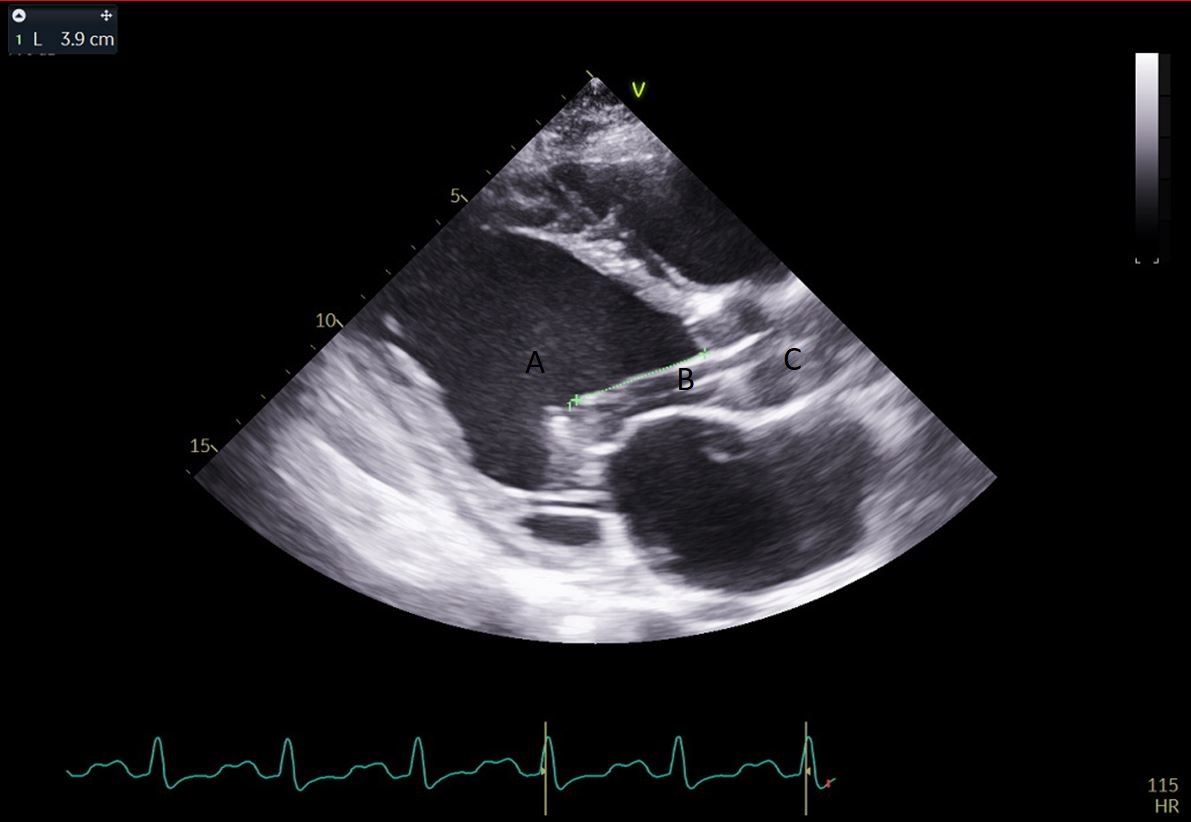

Fig. 7.A parasternal long axis view on a transthoracic echocardiogram. The distance from the Impella inlet to the aortic valve is measured and noted to be 3.9 cm. (A) LV Cavity. (B) Impella. (C) Ascending aortic root.